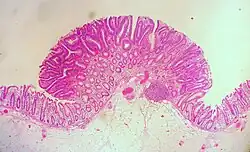

| Tubular adenoma | 2% at 1.5 cm[12] | Low to high grade dysplasia[13] | Over 75% of volume has tubular appearance.[14] |

Neoplastic polyps of the bowel are often benign hence called adenomas. An adenoma is a tumor of glandular tissue, that has not (yet) gained the properties of cancer.

The common adenomas of the colon (colorectal adenoma) are the tubular, tubulovillous, villous, and sessile serrated (SSA).[18] A large majority (65–80%) are of the benign tubular type with 10–25% being tubulovillous, and villous being the most rare at 5–10%.[9]

Micrograph of a tubular adenoma, the most common type of dysplastic polyp in the colon

Micrograph of a tubular adenoma, the most common type of dysplastic polyp in the colon -

Micrograph of a tubular adenoma – dysplastic epithelium (dark purple) on left of image; normal epithelium (blue) on right. H&E stain.

Micrograph of a tubular adenoma – dysplastic epithelium (dark purple) on left of image; normal epithelium (blue) on right. H&E stain. -